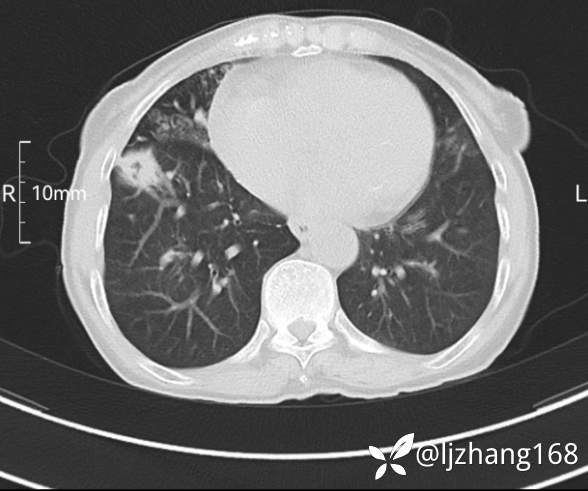

74岁女患,反复咳嗽2月,右肺空洞性病变,炎症OR肿瘤(有病理)

简要病史:2月前开始受凉后出现咳嗽,咳少许白色粘液痰,痰不易咳出,无痰中带血及咯血,无畏寒发热,外院胸部CT提示右下肺空洞病变,脓肿可能性大,常规抗感染治疗效果不佳。既往否认“糖尿病”等病史,有高血压基础病史,无吸烟史。

辅助检查:胸部CT右肺下叶前基底段结节并空洞

临床诊断:右肺空洞:脓肿?